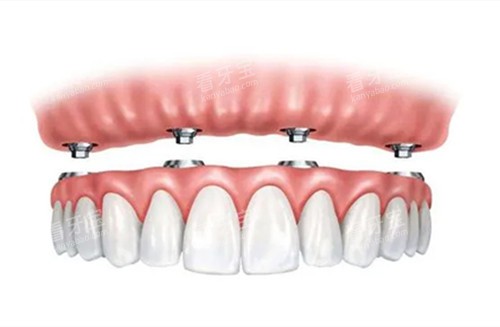

全口吸附性义齿是一种采用特殊设计的修复体,通过功能性印模技术和边缘封闭系统,在口腔内形成稳定的负压吸附力,使假牙能够紧密贴合牙槽骨黏膜表面。与传统活动假牙相比,它的稳固性和舒适度都有显著提升,外观也更接近自然牙齿。